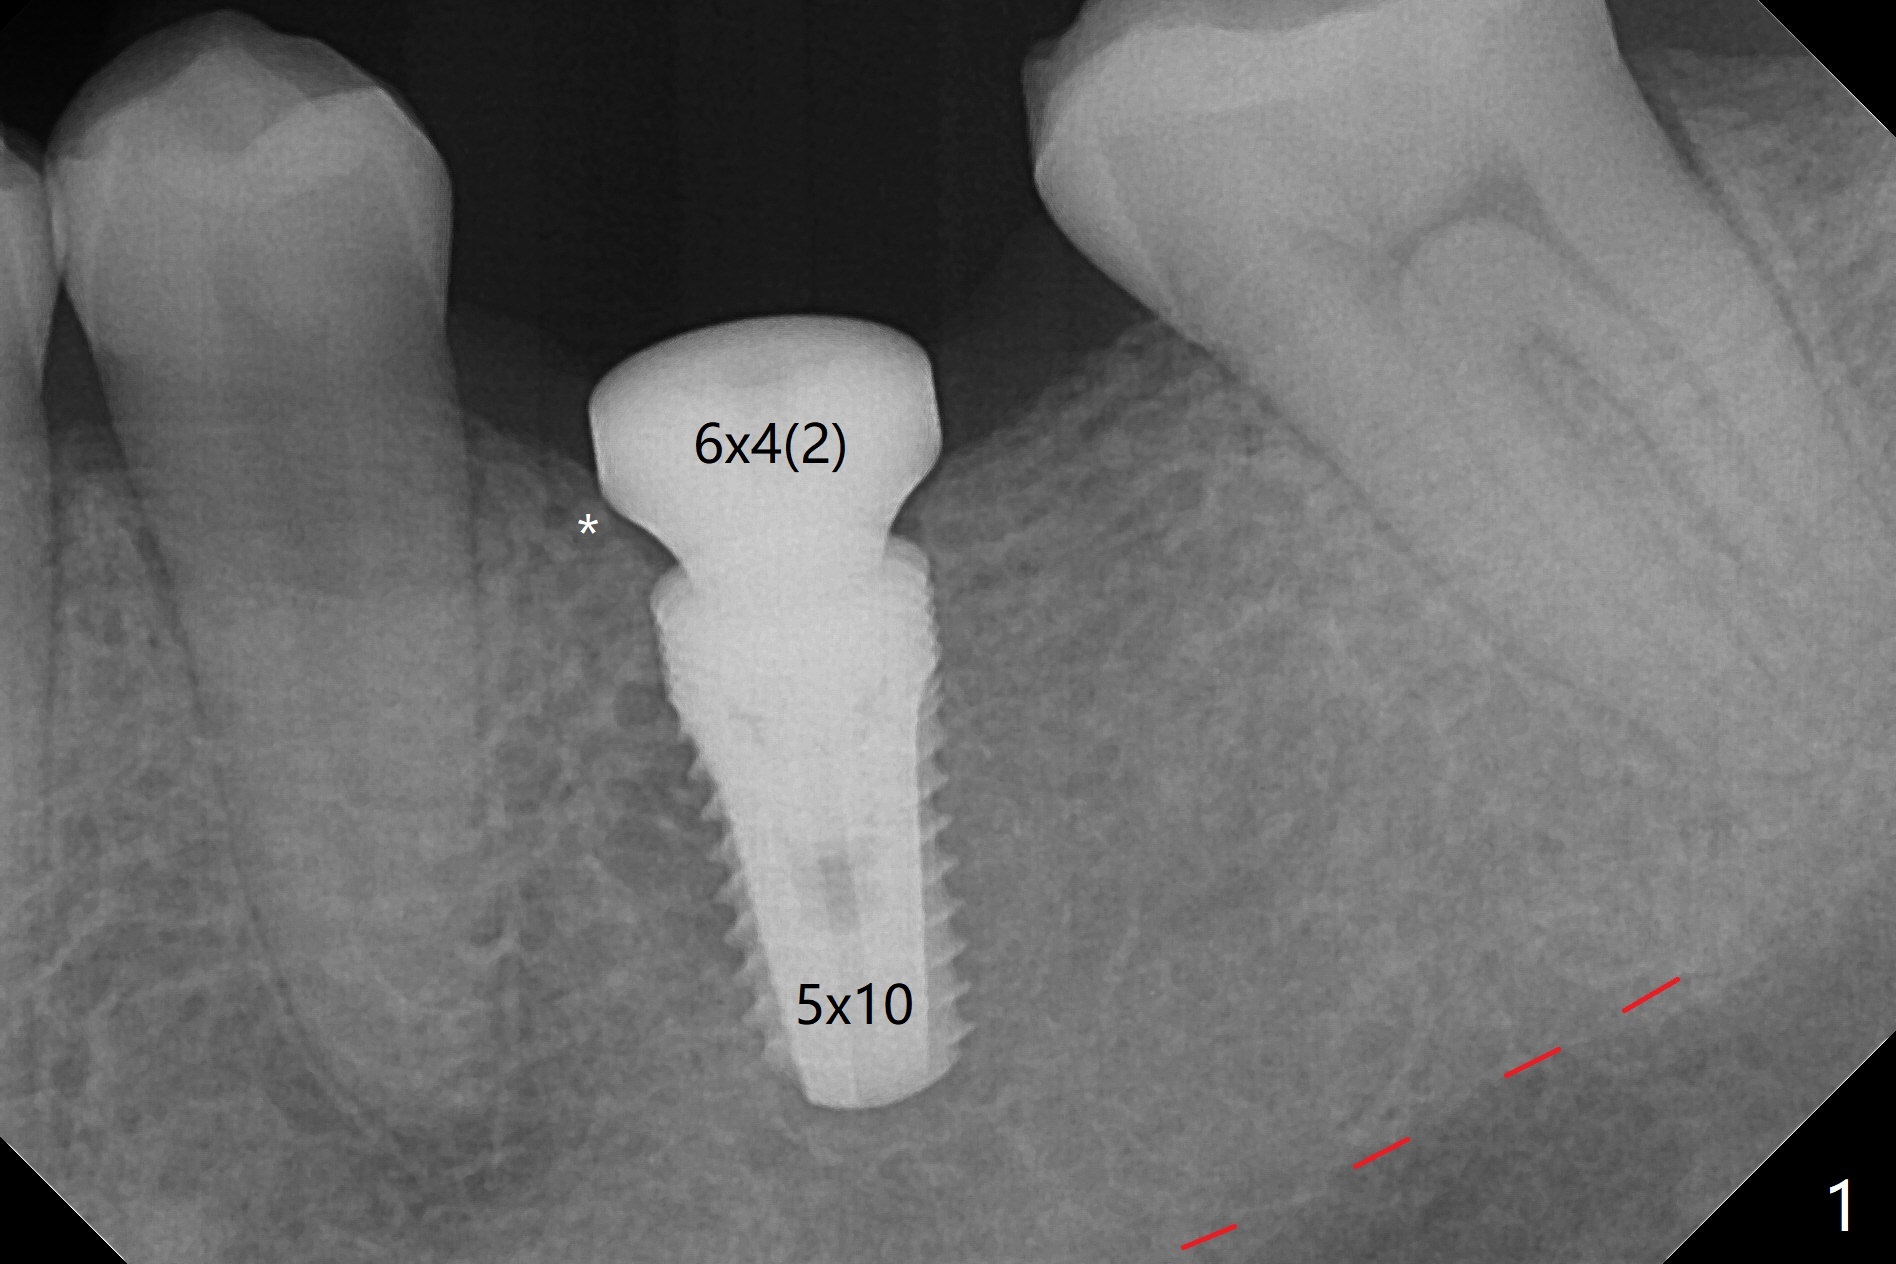

50岁男,左下6牙槽骨宽,但是骨密度低。开始使用导板和小钻头,植体(5x10毫米)扭力大,改用正常钻头,扭力仍高,使用功螺纹后,扭力~35Ncm;使用6毫米profile drill后,放置6x4(2)毫米愈合基台,后者好像与近中牙槽嵴接触(图一:*)。取出基台不顺利,接着放置5x5(3)毫米基台,无法拧紧,取出时,把植体带出来。最后把植体推入钻洞,没有任何扭力,放置愈合帽和Osteogen Plug,缝合(图二,三),牙周敷料,但愿能愈合。在骨质密度低时,放置不合适基台(太宽,太短),可能造成植体松动,脱落,失败。术后十二天牙周敷料脱落,伤口正在愈合(图四(曾经使用环形刀))。术后四个月植体仿佛已经整合(图五),切开放置6.2x5(3)毫米愈合基台,好像与近中牙槽嵴接触太紧(图六)。12天后放置修复基台,似乎就位(图七),其实我们使用取模帽放置基台,非常容易,取模也方便。基台牙冠就位也容易(图八)。螺丝拧紧25Ncm/厂家建议35Ncm。